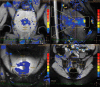

High-intensity focused ultrasound (HIFU) is a minimally-invasive and non-ionizing promising technology and has been assessed for its role in the treatment of not only primary tumors but also metastatic lesions under the guidance of ultrasound or magnetic resonance imaging. Its performance is notably effective in neurologic, genitourinary, hepato-pancreato-biliary, musculoskeletal, oncologic, and other miscellaneous applications. In this article, we reviewed the emerging technology of HIFU and its clinical applications.